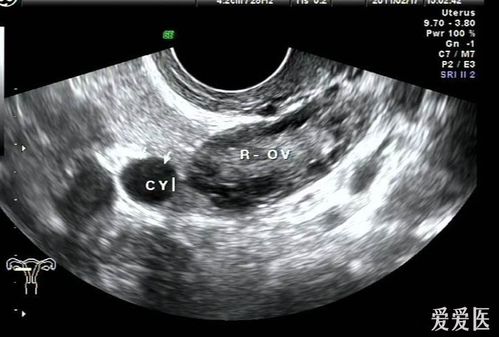

2.输卵管系膜囊肿患者应该定期B超追踪其变化,并严格卧床休息。以避免腹压增高及突然进行腹部检查。